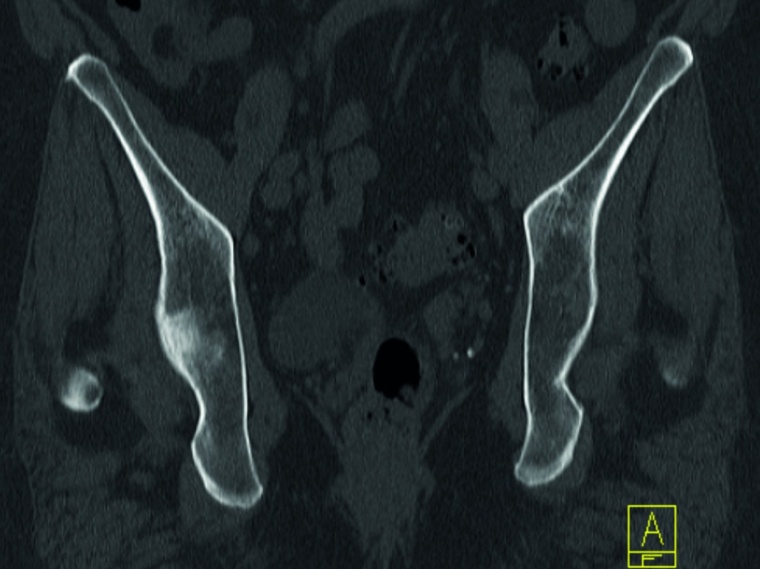

Sakrummetastasen: Stabilitätsgefährdende Metastasen am Sakrum (Abb. 3a) und am hinteren Beckenring werden zumeist mit einer mono- oder bilateralen vertebropelvinen Abstützung versorgt (Abb. 3b). Insbesondere das Os sacrum kann so aus der lasttragenden Kette herausgenommen werden. Vor allem bei Mammakarzinommetastasen kann mit der nachfolgenden Radiatio häufig eine so stabile Rekalzifikation erzielt werden (Abb. 3c), dass mitunter bei Beschwerden über dem Fixateur besonders bei schlanken Patienten eine Metallentfernung erwogen werden kann. Sollte das dorsale Os ileum mit betroffen sein (Abb. 4a) kann bei entsprechenden anatomischen Voraussetzung (Abb. 4b) auch weiter ventral auf den Beckenkamm abgestützt werden (Abb. 4c).